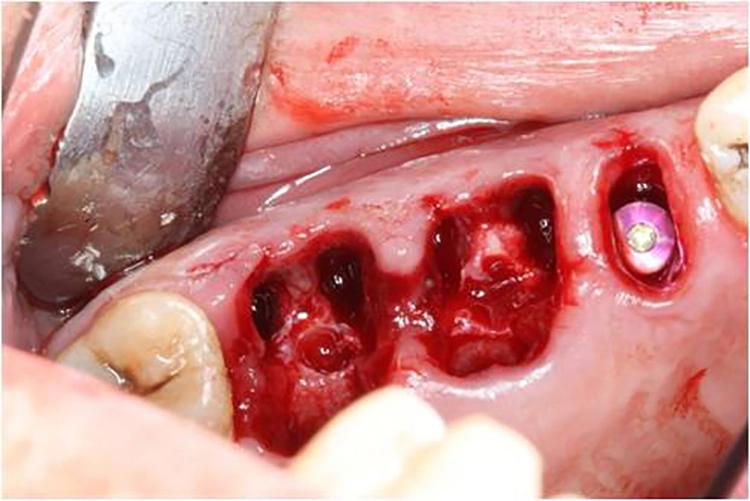

5. Multiple Sofortimplantationen in Zusammenhang mit internem Sinuslift

Beim vorliegenden 54-jährigen Patienten mussten aufgrund von lokaler Parodontitis die Zähne 25, 26 und 27 entfernt werden. Im apikalen Bereich lag jedoch gesunder Kieferknochen vor, sodass eine Sofortimplantation möglich war. Aufgrund der guten Einsichtbarkeit des Operationsgebietes nach Zahnextraktion konnte in diesem Fall flapless vorgegangen werden.

In regio 26 konnte das Implantat dabei komplett apikal im gesunden Knochen verankert werden. In regio 27 jedoch wurde lediglich eine Restknochenhöhe von 8 mm bestimmt. In diesem Fall wurde die Sofortimplantation mit einer internen Sinusbodenelevation nach Summerset kombiniert.

Da zur Aufweitung der Trifurkation die Densah Versah Burs im Rückwärtslauf eingesetzt wurden, kann durch die Osseodensifikation auch der Kieferhöhlenboden bis zu einem bestimmten Umfang mit dieser Technik der Knochenverdrängung angehoben werden. Wird die Kieferhöhle tatsächlich eröffnet, kann auch Knochenersatzmaterial durch den Bohrstollen in die Kieferhöhle augmentiert werden, unter der Voraussetzung einer intakten Kieferhöhlenmembran.